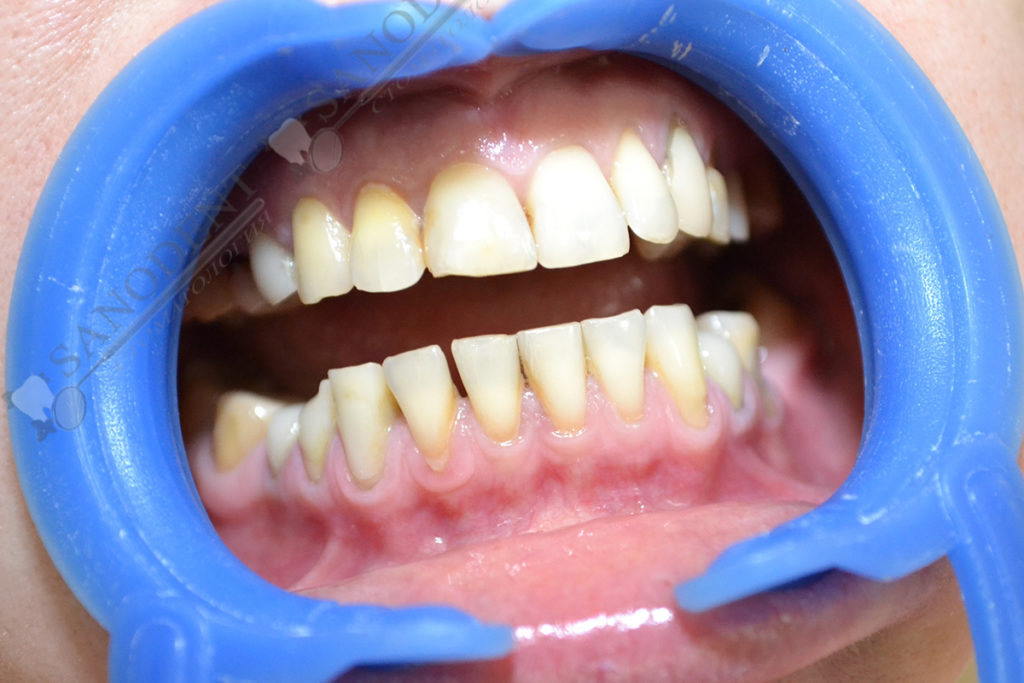

Протезирование керамическими винирами E-max, повышение эстетики улыбки.

- внешний вид до лечения